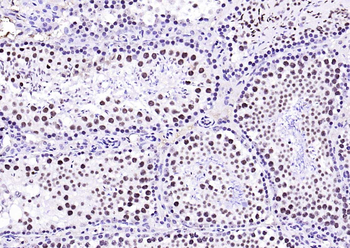

IHC staining of FFPE human brain with Ubiquitin antibody (clone PBQN-1). Required HIER: boil tissue sections in pH9 10mM Tris with 1mM EDTA for 10-20 min followed by cooling at RT for 20 min.